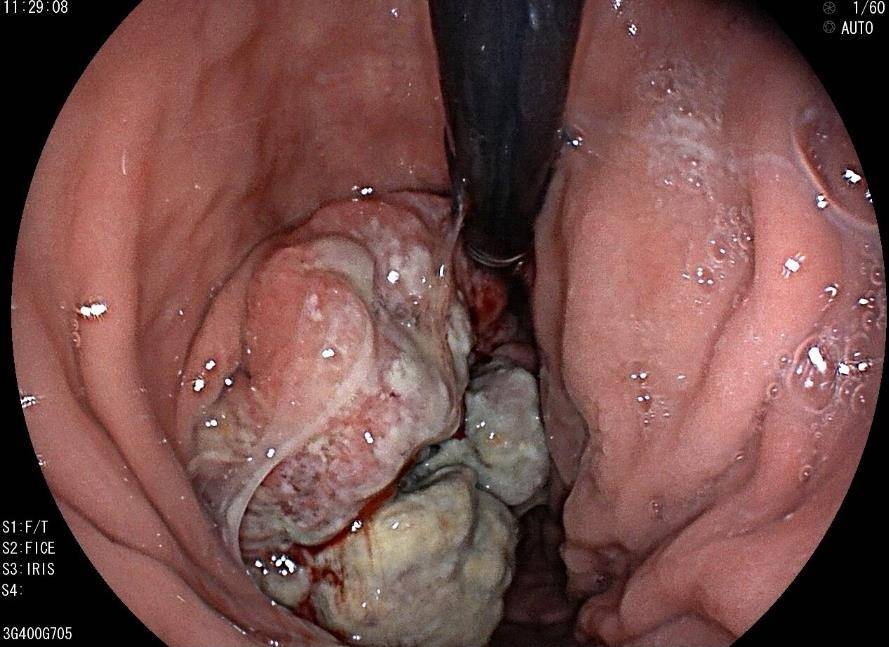

胃镜:贲门开闭可,齿状线距门齿40cm,贲门左侧壁见隆起型肿物延伸至胃底,贲门、胃底、胃体上段后壁见巨大肿物,长径约10cm,大小约10*7cm菜花样隆起,中央凹陷溃疡形成,表面覆厚秽苔,易出血,活检4块质糟脆。胃窦、胃角、胃体小弯中下段黏膜粗糙,红白相间以白为主,局部可透见黏膜下血管,胃窦小弯活检1块。